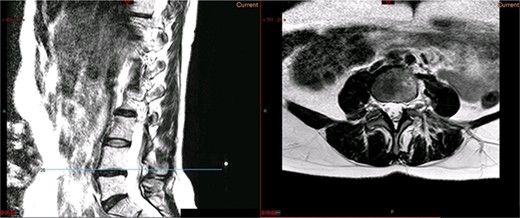

A magnetic resonance imaging (MRI) scan performed in October 2013 (Fig. 1) identified non-compressive, degenerated discs at L4/5 and L5/S1 vertebral levels. However, clinically as the patient was more tender over the left SI joint and the pubic symphysis (Fig. 2), a left sacroiliac joint fusion and symphysis pubis plating procedure was performed in August 2014 (Fig. 3). Following a short period of relief, the pain returned. Subsequently, the patient underwent a 360° fusion (front and back) of the L4/L5 and L5/S1 discs in August 2015 (Fig. 4), a year following the previous surgery. Once again, following a brief period of relief, the symptoms returned. The assumption then was that the initial fusion of the left sacroiliac joint had failed. Therefore, a revision fusion of the left sacroiliac joint and a primary fusion of the right sacroiliac joint was undertaken in August 2017 (Fig. 5).

Preoperative X-ray of the pelvis: preoperative X-ray of the pelvis, performed in March 2014, showing no implants yet in place.